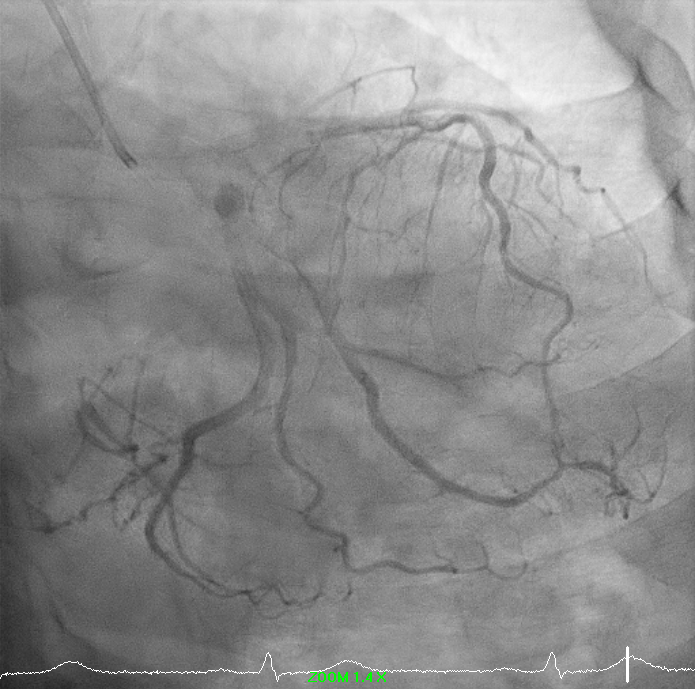

Right-dominant system. Proximal LAD shows 50% moderate calcified disease. Proximal LCx has 50% stenosis with severe calcification. RCA demonstrates severe diffuse proximal–mid 70% stenosis with moderate calcification and distal severe ISR-CTO with heavy calcification and minimal antegrade flow. Impression: Complex RCA ISR-CTO as culprit with moderate pLAD/pLCx disease.

8.avi

9.avi

11.avi